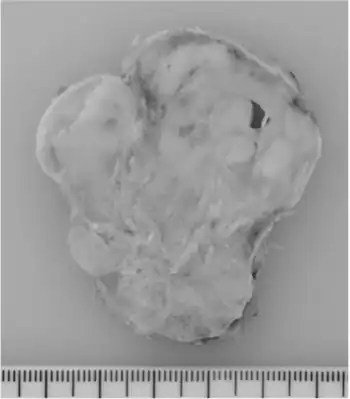

| Ossifying fibromyxoid tumor shows a well-circumscribed, gray-white, multinodular appearance | |

An ossifying fibromyxoid tumor is a type of myxoma. It presents in the extremities more frequently than the trunk.[1] It is derived from mesenchyme.[2] Appearance in the head and neck is rare, but has been reported.[3] Its malignancy has been characterized as "intermediate".[4]